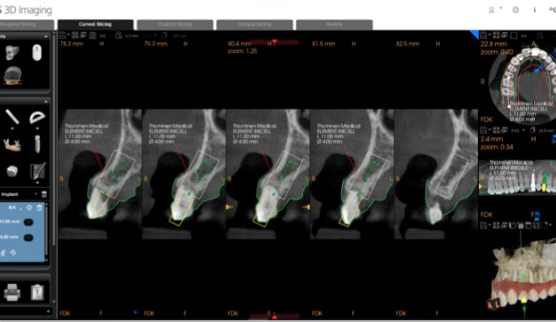

Prosthetic-driven implant planning in CS 3D Imaging software showing merged CBCT and intraoral scan data

CBCT analysis within CS 3D Imaging software showing cross-sectional views of the implant site

Step 2 CBCT volume analysed in CS 3D Imaging software. Cross-sectional views confirm bone dimensions and root resorption on the UL3.

Step 3 — Prosthetic-driven implant planning. This is the key step. The CS 3D Imaging Prosthetic-Driven Implant Planning module automatically merged the CBCT volume with the intraoral scan — aligning hard tissue (bone) with soft tissue (gingiva and teeth) in a single view. The implant was then positioned using a crown-down approach: the ideal restoration position determined the implant axis, not the other way around.

CS 3D Imaging automatically merging CBCT and intraoral scan data for prosthetic-driven planning Implant position planned using crown-down approach in CS 3D Imaging

Step 3 The Prosthetic-Driven Implant Planning module in CS 3D Imaging software automatically merges the CBCT and intraoral scan. The implant is positioned based on the ideal crown position — not just the available bone.